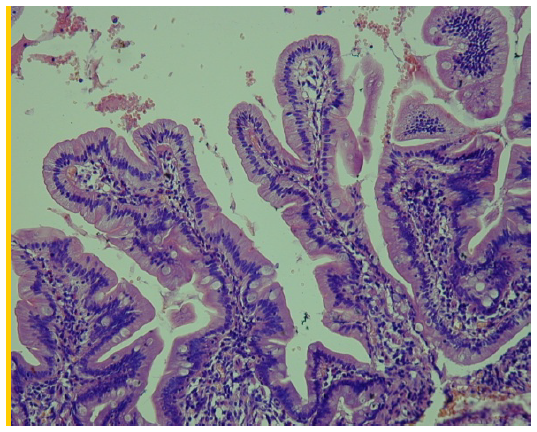

В ряде случаев в слизистой оболочке двенадцатиперстной кишки отмечалось формирование лимфоидных фолликулов с четкой клеточной структурой, местами со слабовыраженной макрофагальной реакцией в центральных отделах (рис. 2).

Рис. 2. Стенка двенадцатиперстной кишки. Лимфоидный фолликул в толще слизистой оболочки. Окраска гематоксилином и эозином ×4